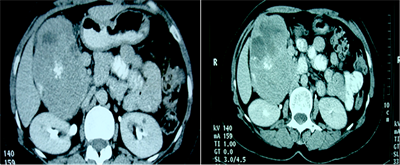

CT scan, performed with oral and intravenous contrast, upheld the findings of ultrasound revealing a large heterogeneous tissular mass in the pancreatic head, with central necrosis and calcifications (Figure 2). It showed an intense heterogeneous enhancement in the arterial phase. This mass was bounded in front by the gall bladder which is repressed, in the back by the right kidney with apparent para renal fat invasion and laterally, by digestive structures (small bowl and colon). The corporeal and caudal portions of the pancreas were normal. Moreover, intrahepatic and extrahepatic bile ducts were not dilated and no metastatic localisation was detected.

Figure 2. Abdominal computed tomography scan. (a) Computed tomography scan with oral contrast showing the calcifications within the pancreatic head mass which is repressing the gall bladder; (b) Computed tomography scan performed after oral and venous contrast in the portal phase showing an intense heterogeneous enhancement associated with necrosis within the mass; (c) Computed tomography scan performed after oral and venous contrast in the tardive phase.